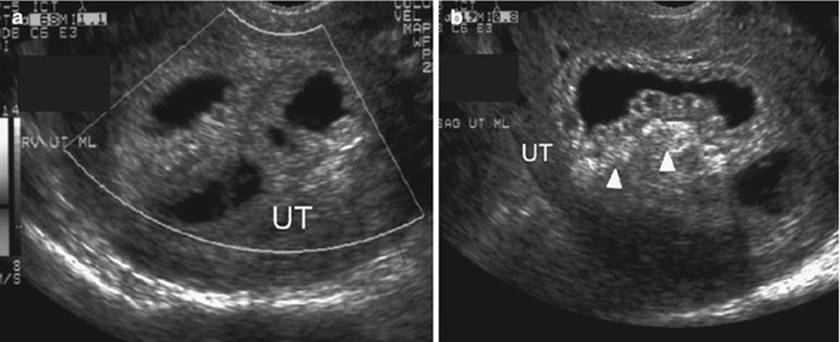

Abdominal sonography can make the diagnosis of an intussusception in an adult when the characteristic sign of a “target-like” lesion or “bull’s eye” lesion is shown, similar to the CT findings, and is sometimes enough for the definitive diagnosis [83]. The classic features of intussusception include “target,” “doughnut,” or “crescent-in-doughnut” signs on a transverse view and the “pseudokidney” sign in the longitudinal view (Fig. 7.8), or multiple concentric rings of intussusceptum (Fig. 7.9) or multiple concentric vascular signals in thickened intussuscipiens (Fig. 7.10) [72, 73, 95–97]. The central echogenic area is produced by the mucosa of the intussusception, which is surrounded by a hypoechoic ring representing the walls of both the intussusceptum and the intussuscipiens [98]. This variability in appearance is largely due to the scanning level, the amount of intussuscepted mesentery, the degree of bowel wall edema, and the presence of a pathologic lead point and lymph nodes. Ultrasound is an operator-dependent technique whose utility may be limited by obesity and air in distended bowel loops.

Fig. 7.9

Jejunojejunal intussusception during late pregnancy in a 33-year-old woman. Transverse gray-scale sonogram showing multiple concentric rings (arrows) representing multiple layers of the innermost intussusceptum, intervening mesenteric fat, and vessels and outer intussuscipiens at the left of the fetal abdomen (arrowheads) [72]

Fig. 7.10

Jejunojejunal intussusception during late pregnancy in a 33-year-old woman. Transverse color Doppler sonogram showing multiple concentric vascular signals in thickened intussuscipiens (arrows) and some vascular spots in the hypoechoic intussusceptum (arrowheads) and echogenic mesentery [72]